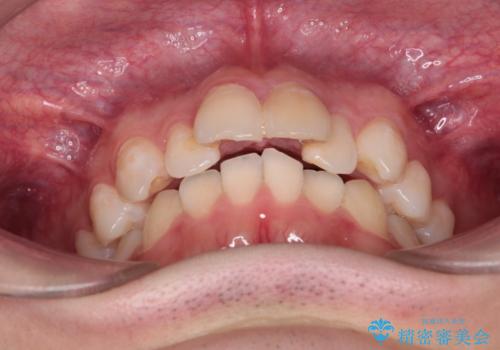

- 前歯が出ていることを主訴に来院されました。

臼歯関係が上顎前突傾向のため、上顎小臼歯を抜歯してインビザラインにて治療を行いました。